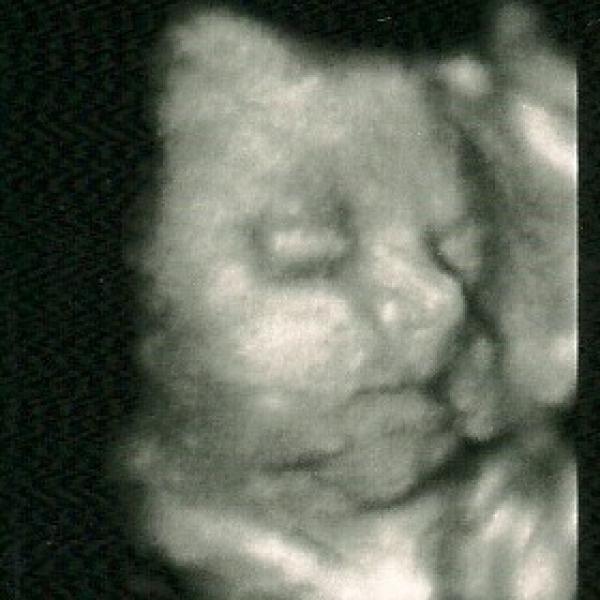

Ahoj maminky,tak máme novou fotečku z 4D utz.A jak těhulkujete?Pohlaďte bříška.papa